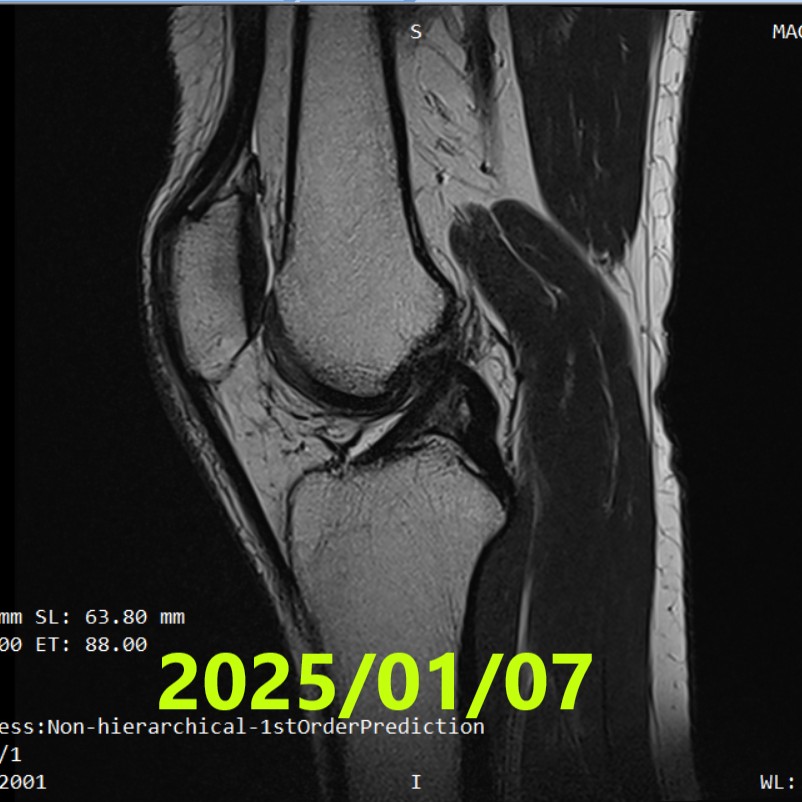

Tercera RM (~21 meses)

- Fecha: 7 de enero de 2025

- Hallazgos: en comparación con la RM #2, la señal del LCA parecía más intensa, lo que sugiere una mayor progresión de la curación

- Evaluación: no alcanzó ACLOAS grado 1

- RM #3 (2025/01/07): sugirió una mayor progresión de la curación (no alcanzó ACLOAS 1)